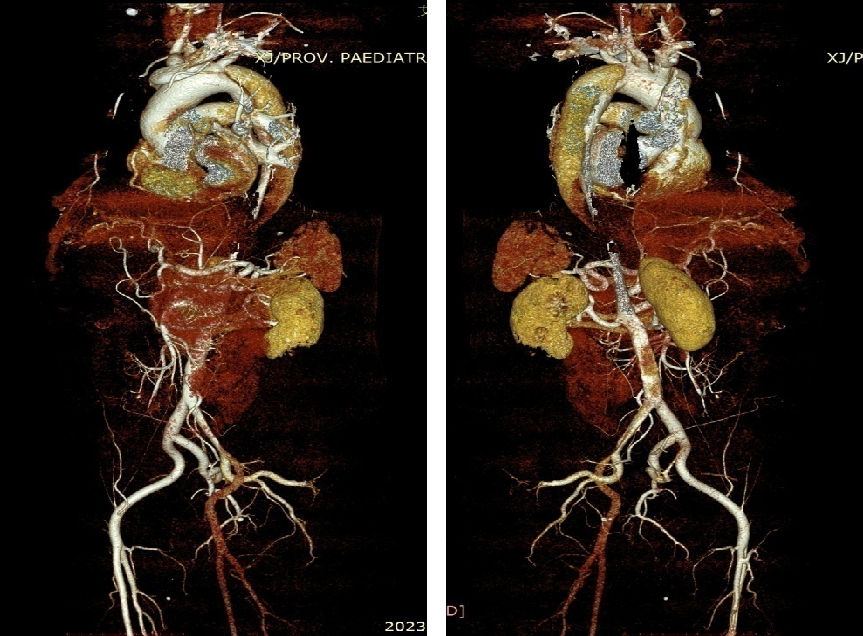

男, 49岁,急性夹层 。2018年11月TEVAR。一月后复查:RTAD 。 2019年1月双开窗。2019年4月2日 复查,结果良好。

▎病例五

男,49岁,急性AD。2019年1月TEVAR,3月RTAD,行全弓置换+支架象鼻。2022 年1月25日术后复查,结果良好。